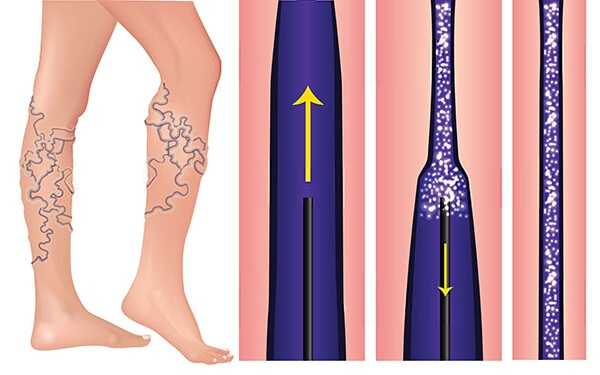

- Удаление сосудистых звездочек на ногах лазером

- ЭХО-склеротерапия вен

- Комбинированная флебэктомия

- Минифлебэктомия

- Удаление сосудистых звездочек на ногах

- Флебэктомия вен нижних конечностей

- Пенная склеротерапия вен

- Эндовазальная лазерная коагуляция вен (ЭВЛК)

- Микросклеротерапия

- Склеротерапия вен

- Флебология